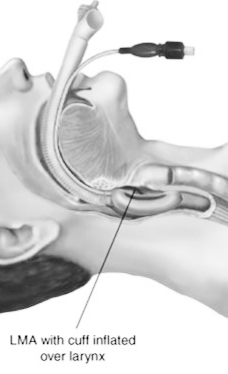

- Laryngeal mask airway

- Supraglottic airways: laryngeal mask airway LMA